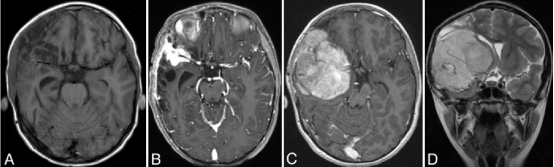

送进急诊时,苏珊的情况已经岌岌可危。影像学检查清楚地显示,出血来源于右侧大脑中动脉三分叉处的一个破裂动脉瘤,由此引发了严重的右额叶出血和蛛网膜下腔出血。这是儿童神经外科中最为险急的情况之一,每延误一秒,脑组织受损的范围就可能扩大一分。

A:非增强CT扫描,显示右额叶出血,侧裂内可见致密蛛网膜下腔出血。

B:右侧颈内动脉脑血管造影斜位片,显示一个5毫米大小的大脑中动脉(MCA)三分叉处动脉瘤。

C:右侧颈内动脉脑血管造影斜位片,显示MCA动脉瘤已成功实施血管内弹簧圈栓塞术